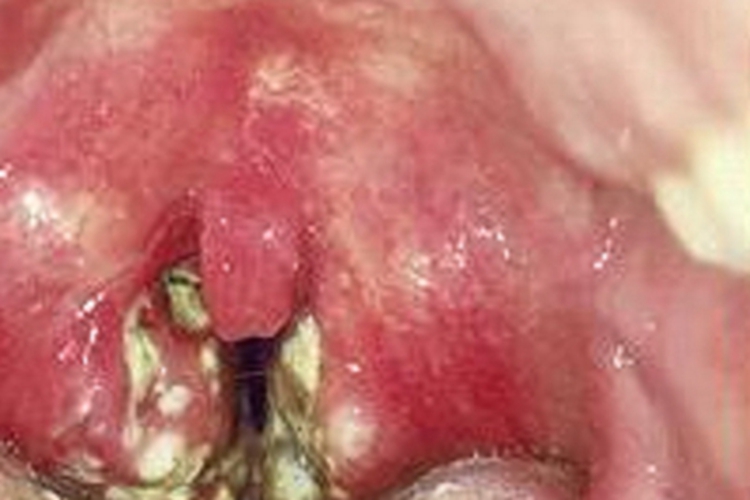

脓毒型猩红热可见咽部表现为局部表面明显红肿,呈疙瘩样损害,颜色鲜红,分布密集,排列无规则,可聚集成团,部分表面渗出物较多,形成脓性假膜,呈灰绿色。